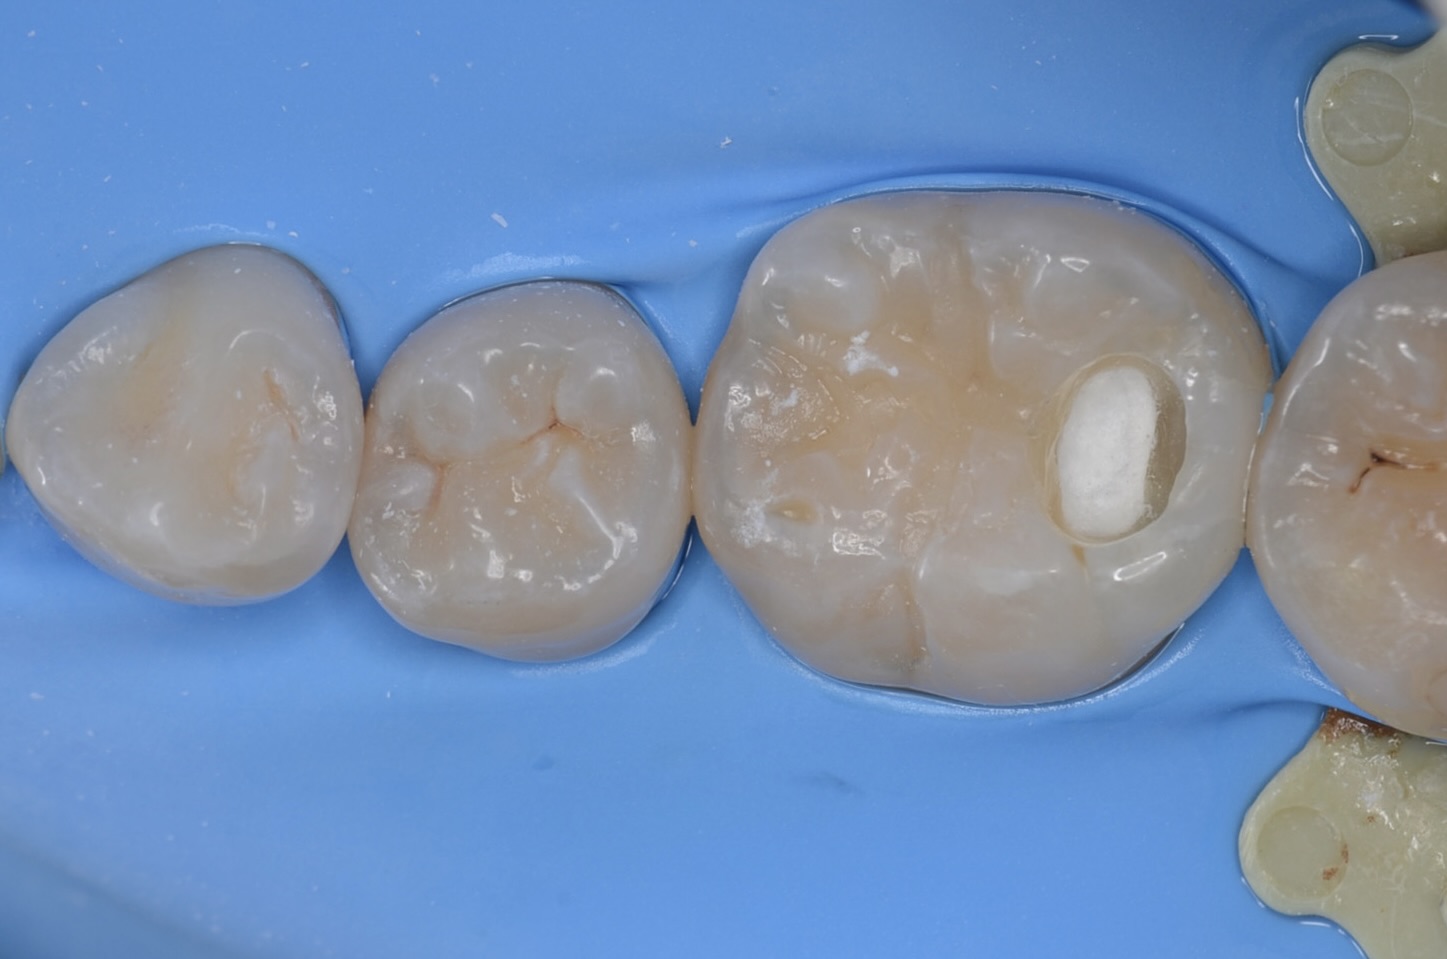

MTAセメント

露髄面にMTAセメントを充填しました。 -

スーパーボンド

スーパーボンドでMTAセメントを覆います。 -